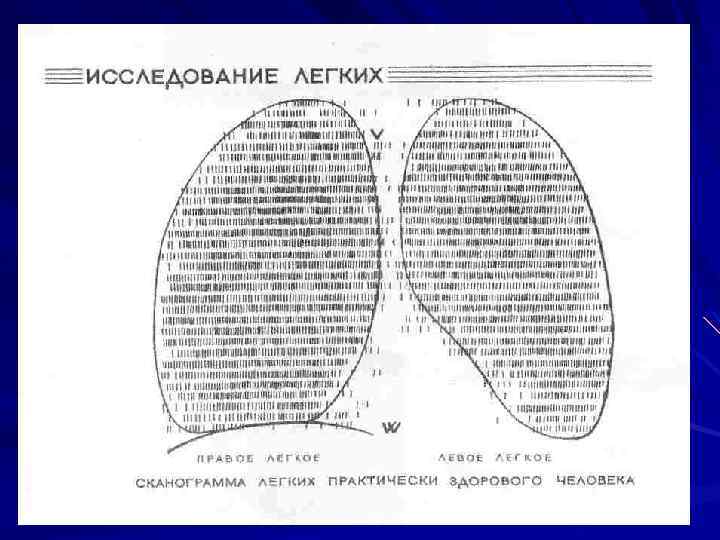

-Функция внешнего дыхания (нормативы): ЖЕЛ: муж. – 4 – 5 л. Жен. – 3 – 4 л. ОФВ 1: муж. – 3 – 4 л. Жен. – 2 – 3 л. Индекс Тиффно: ОФВ 1/ЖЕЛ х 100 (70 – 85%). МВЛ: муж. – 100 – 125 л мин. жен. - 80 – 100 л мин. - Сканирование легких (радиоизотопное исследование).